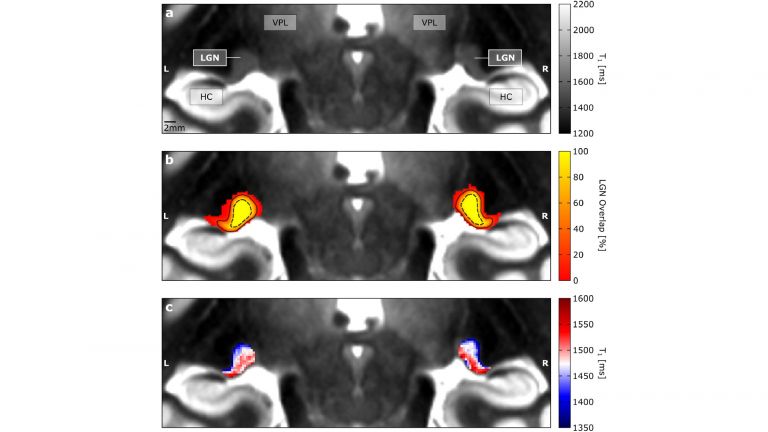

Diese Schwierigkeit, den visuell-sensorischen Thalamus im Detail zu untersuchen, hat das Verständnis über die Funktionsweise der visuellen Sinnesverarbeitung in der Vergangenheit stark beeinträchtigt. Christa-Müller Axt ist Doktorandin und beschäftigt sich in der Abteilung von Neurowissenschaftlerin Prof. Katharina von Kriegstein an der TU Dresden mit dem visuell-sensorischen Thalamus. Durch Zufall entdeckte die Doktorandin in Neuroimaging-Daten Strukturen, die den beiden visuell-sensorischen Thalamus-Teilen ähnelten. Die Neuroimaging-Daten waren einzigartig, da sie eine äußerst hohe räumliche Auflösung aufwiesen und mit einem speziellen Magnetresonanztomographen (MRT) am MPI-CBS in Leipzig aufgenommen wurden, wo von Kriegsteins Gruppe neurowissenschaftliche Studien zu Legasthenie durchführte. Christa Müller-Axt verfolgte diese Entdeckung in einer Reihe weiterer neuartiger Experimente, bei denen sie in-vivo-(am lebenden Objekt gewonnene) und post-mortem-(am toten Objekt gewonnene) MRT-Daten mit hoher räumlicher Auflösung sowie post-mortem Histologie (Wissenschaft von den Geweben des menschlichen Körpers) analysierte, und war sich bald sicher, die beiden Teile des visuell-sensorischen Thalamus entdeckt zu haben.

Die Ergebnisse zeigen, dass die zwei Teile des visuell-sensorischen Thalamus durch unterschiedliche Mengen an weißer Hirnsubstanz (Myelin) gekennzeichnet sind. Diese Information lässt sich in den neuartigen MRT-Daten erkennen und kann somit zur detaillierten Untersuchung des visuell-sensorischen Thalamus beim lebenden Menschen verwendet werden.